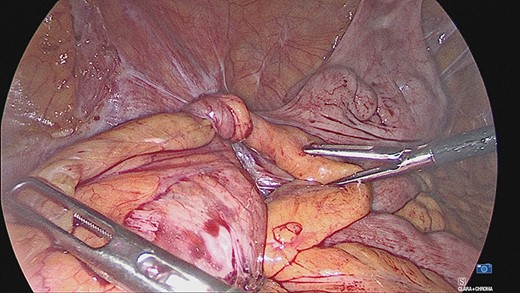

The appendiceal mucocele was visualised during the laparoscopic procedure. The adhesions surrounding the apex of the mucocele were released. There appeared to be volvulus of the appendix (Fig. 3). The main body of the appendix was normal with no evidence of malignancy seen during the surgery. On this basis, a right hemicolectomy was not performed. The appendix was amputated at the base and removed with the base tied (Fig. 4).